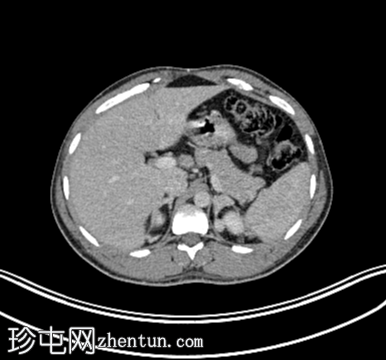

轴位增强CT

10.png

肾上腺:双侧肾上腺结节性增厚,FDG摄取增高。

为排除肿瘤病因或恶性淋巴结肿大,建议行PET检查。PET显像显示双侧肾上腺结节性增大,符合肾上腺增生,未见转移性病变。